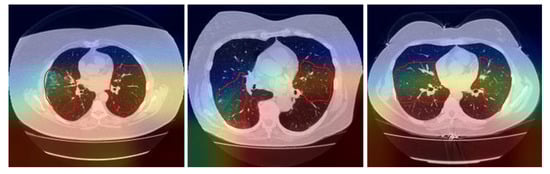

2.1. Data Preprocessing

4. Discussion